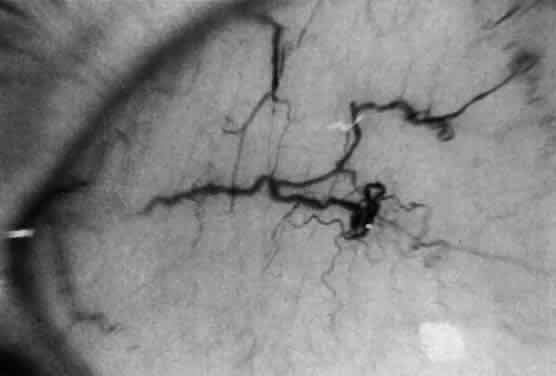

Corneal clouding (Fig. 10), hyperopic astigmatism, and a mild retinopathy with surface-wrinkling maculopathy (Fig. 11) appear to be the constant ocular triad.75 Some patients have retinal vascular tortuosity, optic nerve head swelling (Fig. 12), visual field defects, and abnormalities in color vision. Visual complaints are uncommon.

Fig. 10. Mild corneal clouding in a child with mucolipidosis III. (Traboulsi E, Maumenee I: Ophthalmologic findings in mucolipidosis III. Am J Ophthalmol 102:529, 1986)

Fig. 11. Surface-wrinkling maculopathy in a patient with mucolipidosis III. (Traboulsi E, Maumenee I: Ophthalmologic findings in mucolipidosis III. Am J Ophthalmol 102:529, 1986)

Fig. 12. Optic nerve head swelling in a patient with mucolipidosis III. (Traboulsi E, Maumenee I: Ophthalmologic findings in mucolipidosis III. Am J Ophthalmol 102:529, 1986)